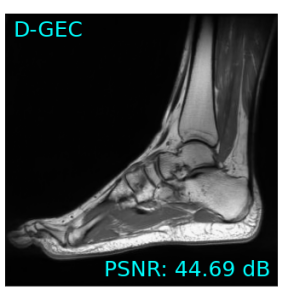

Single-coil results: Table 1 shows that D-GEC outperformed D-VDAMP in all single-coil experiments and outperformed PnP-PDS in all but SSIM at . Figure 5 shows an example of the wavelet coefficients input to D-GEC’s denoiser at the 10th iteration, and their error relative to the true coefficients. Figure 3 shows the evolution of the standard deviation at the input to D-GEC’s denoiser in each subband; there is a good agreement between true and predicted values. Figure 6 suggests that the subband errors are Gaussian. Figure 4 shows image recoveries and error maps for one test image at .